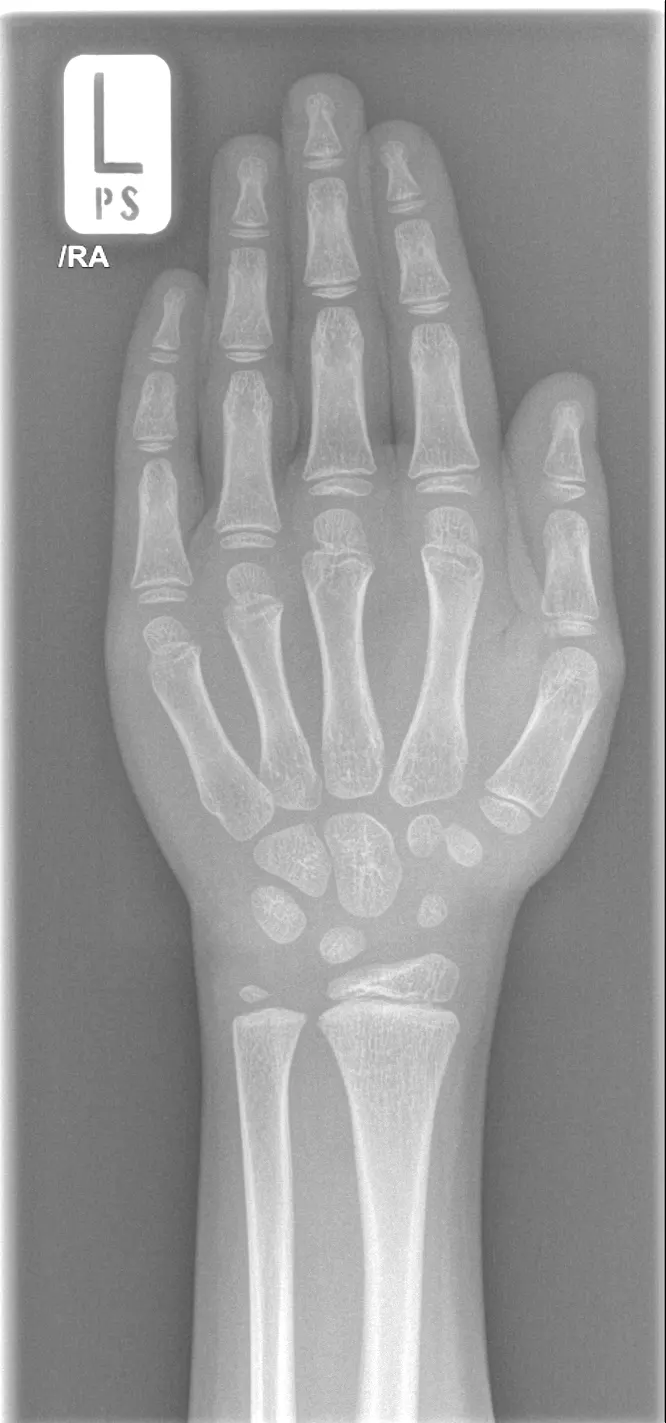

How it looks in practice

See how Carebot works in practice. Compare the image with AI and without AI.

Without Carebot

With Carebot

Overview of detected findings

Analyzes an X-ray image of the hand and wrist to determine bone age based on the degree of skeletal maturity

Status of growth plates

Morphology and size of the hand and wrist bones

Presence and maturity of ossification centers

Overall pattern of skeletal maturation